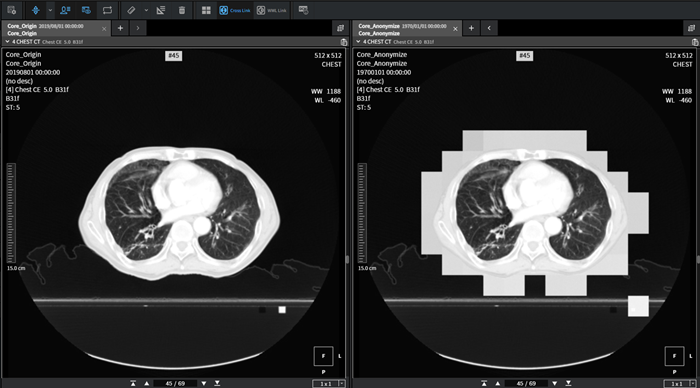

AVIEW 가명화 서버는 의료 데이터 가명화 처리·관리를 위한 솔루션이다. CT, MRI 등 모든 데이터의 환자정보를 표준에 맞게 가명처리를 하고 동시에 환자의 신체표면을 가명화를 함으로써 특정인임을 식별할 수 없도록 처리한다. 이와 함께 가명화 처리된 데이터를 저장하고 관리하는 폭넓은 서비스를 제공하고 있다.

하지만 '복원기술'을 활용하면 CT 영상 이용해 흉부 표면까지 복원해 개인을 식별해 낼 수도 있다. 이러한 개인정보 노출의 위험을 차단하고 가명정보를 활용한 연구의 활성화를 위해 보건복지부는 지난해 보건의료데이터 가이드라인 개정을 통해 '영상정보 가명처리' 기준을 명확히 했다.

영상정보 이미지상의 특정개인을 식별할 수 있는 신체적 특징은 삭제 또는 모자이크 처리, 표면 가장자리 삭제 등 방법으로 처리해야 한다.